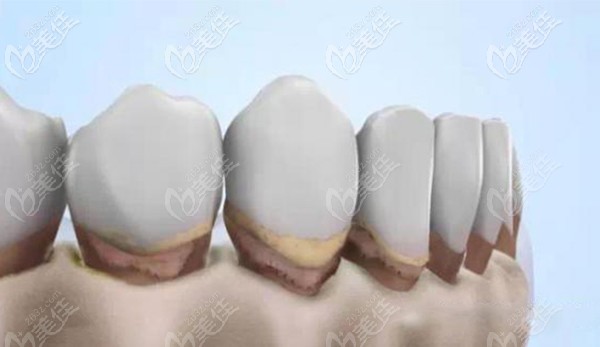

其實做種植牙不怕花的錢多錢少,就怕的是花錢買罪受,比如術(shù)后基臺和種植體的密合性不好,長期如此引起能發(fā)炎疼痛。所以一定要找一家口碑好的醫(yī)院做種植,就像鄭州金水區(qū)的口腔,